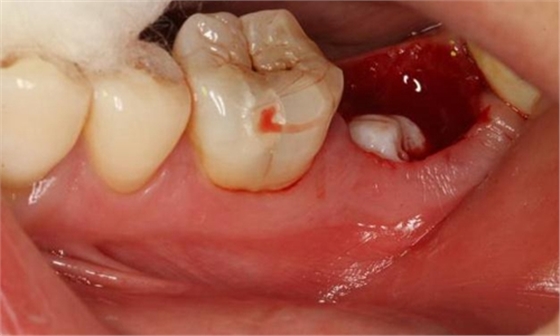

圖9.清理牙槽窩過后。多生牙的牙冠暴露在牙槽窩內(nèi)。